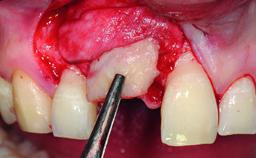

Replacement of a Failing Restored Upper Right Central Incisor, Ridge Preservation and Early Placement of an RC Bone Level Implant

A 23-year-old female, healthy and non-smoking patient had had tooth 11 temporarily restored following a trauma in adolescence. As the patient’s growth had since come to an end and the crown had fractured, she requested an implant-supported restoration of tooth 11. Moreover, the contralateral tooth 21 presented an old composite restoration at the mesial incisal edge. The periodontal tissues were healthy with periodontal probing depth values below 3 mm, but some inflammation was observed around the semi-submerged root of tooth 11.